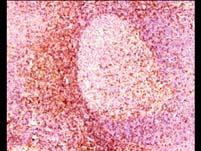

问题 符合小淋巴细胞性淋巴瘤的病理形态特点为()

选项 A.肿瘤起源于B淋巴细胞 B.瘤细胞形态幼稚 C.淋巴窦内充满瘤细胞 D.结结构可全部消失 E.可表达T细胞抗原CD5

答案 ACE